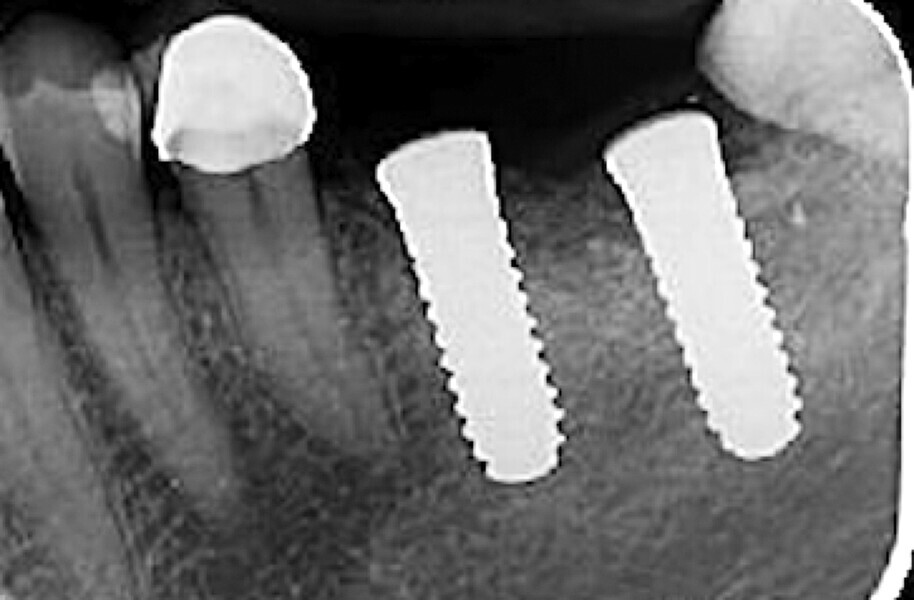

Fig. 34 : Radiographie de contrôle à deux mois.

La crête alvéolaire au niveau du site de la molaire inférieure était trop étroite pour permettre la pose prédictible d’un implant sans une augmentation osseuse préalable. Des implants deux pièces en zircone ont été mis en place, simultanément à une augmentation osseuse latérale, au moyen d’une allogreffe et d’une membrane de collagène résorbable (Figs. 25–34).